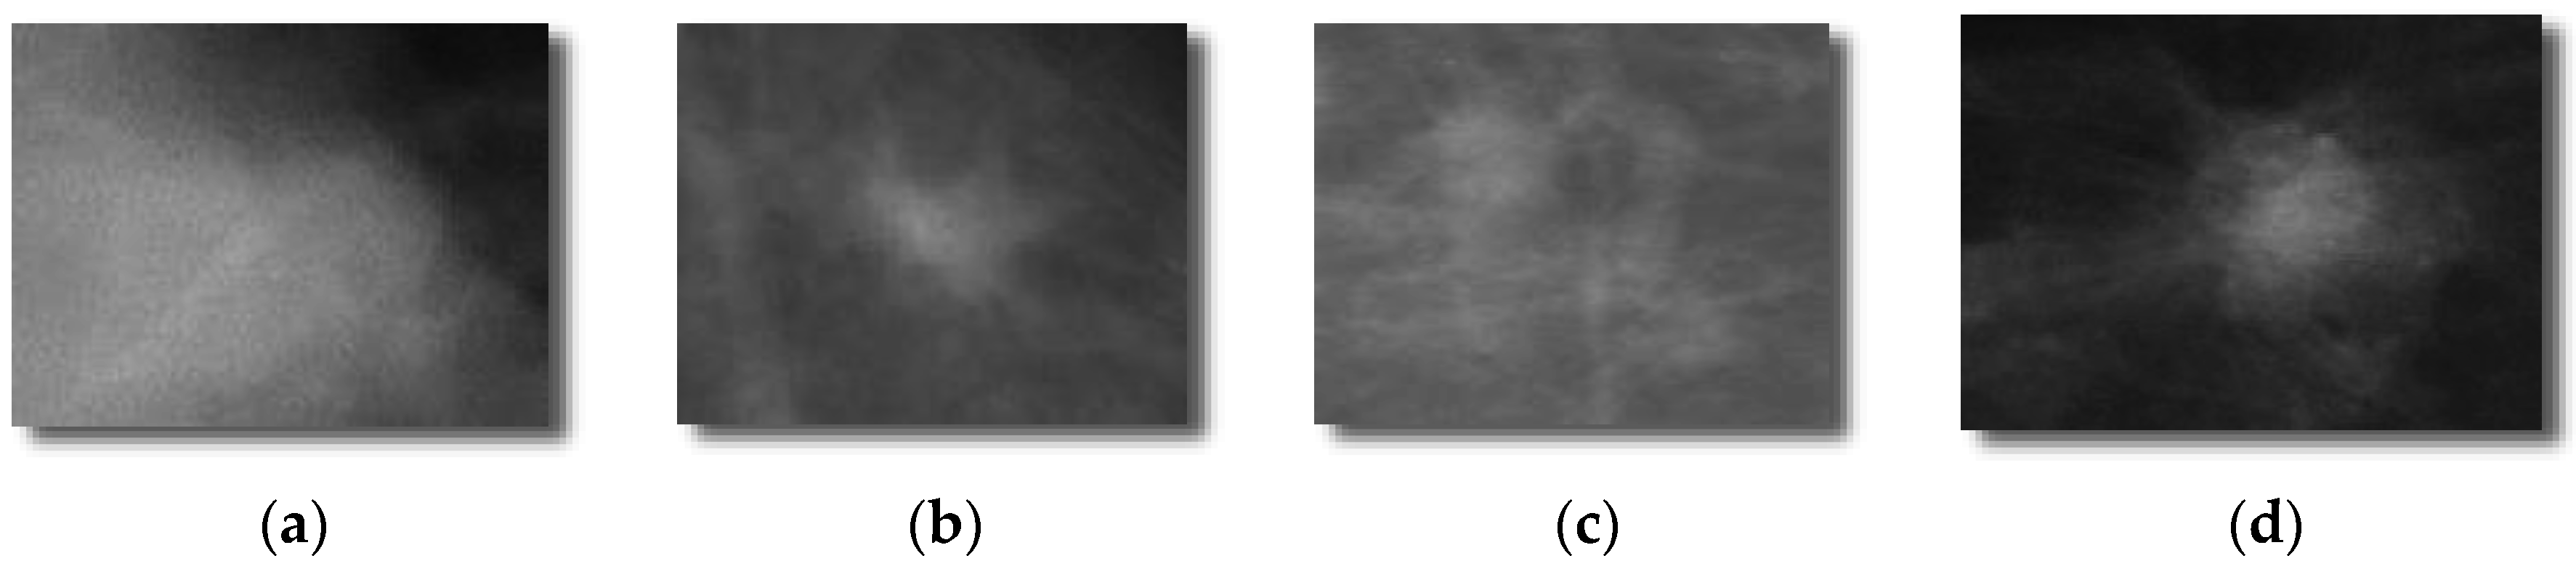

Each selected mammograms were sub-sampled by the average of an 8 × 8 window of pixel values. By combining DDSM and mini-MIAS datasets, a total set of 600 ROIs (i.e., 300 benign masses and 300 malignant masses). The 300 benign and 300 malignant masses were obtained to evaluate the proposed DeepCAD system and to compare the performance with state-of-the-art classification systems. From each image, the region-of-interest (ROI) of size (250 × 250) pixels was extracted by an experienced radiologist. An example of this dataset is shown in

Figure 2.